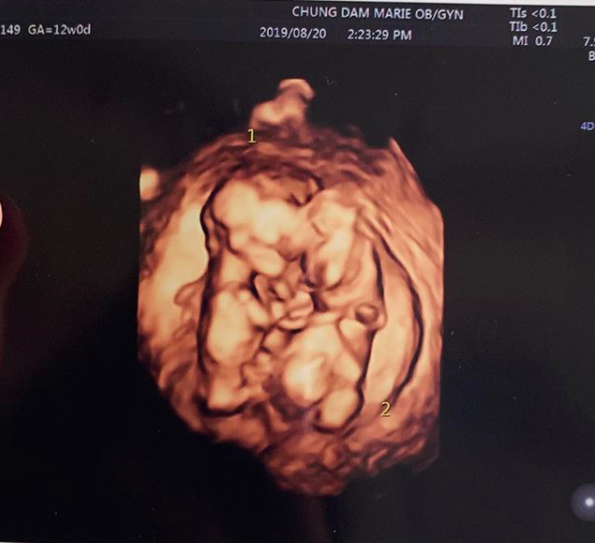

율희는 거듭 고마운 마음을 표현했다. 그는 “둥이들은 이렇게 서로 꼭 붙어 잘 크고있답니다. 다시 한 번 축하해주셔서 감사드려요”라고 했다. 이와 함께 율희는 쌍둥이의 모습이 담긴 초음파 사진을 공개해 눈길을 끌었다.

생각지 못한 쌍둥이 임신에 최민환, 율희 모두 놀랐다. 최민환은 “너무 놀라서 말이 안 나왔다. 이게 정말 내게 일어날 일인가. 이게 내게 하는 말인가. 아무 것도 들리지 않았다. 큰 축복이 있을까 싶었다”고, 율희는 “초음파로 아이들을 처음 보는데 눈물이 났다. 초음파만 봐도 사랑스럽다”고 말했다.